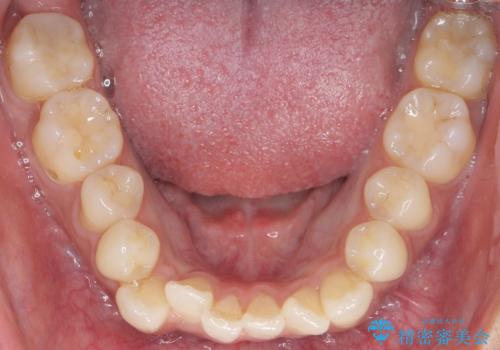

- 奥歯にフロスを通すとにおいがすることを気にされ、来院された患者様です。

精査したところ、奥歯に充填された保険内のコンポジットレジンの適合が悪いことにより、汚れがたまりやすい状態でした。

不適合なレジンを除去し、セラミックインレーによる治療を行いました。(右上76左上67右下7の計5本)